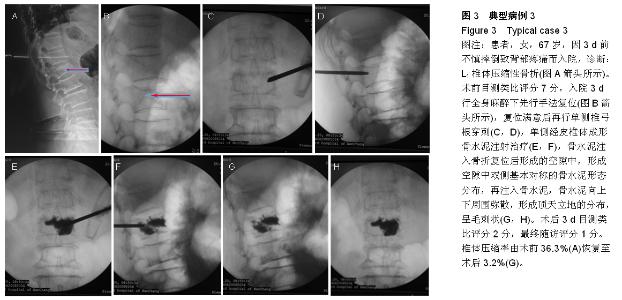

METHODS: A total of 53 patients with single vertebral osteoporotic vertebral compression fractures, who were treated with percutaneous vertebroplasty, were retrospectively analyzed from July 2012 to December 2014. The new method group (32 cases) received manual reduction, underwent unilateral pedicle puncture and bone

cement injection during unilateral percutaneous vertebroplasty under general anesthesia. The conventional method group (21 cases) received conventional percutaneous vertebroplasty.

RESULTS AND CONCLUSION: There was an average of 6-month follow-up (3-14 months). Significant differences in visual analogue scale scores, vertebral compression ratio and kyphosis Cobb’s angle were detected in the new method and the conventional method groups at 3 days post surgery and during final follow-up compared with before surgery (P < 0.01). No significant difference in visual analogue scale scores was found between the two groups (P > 0.05). Compared with the conventional method group, postoperative vertebral compression ratio, kyphosis Cobb’s angle and bone cement leakage rate were significantly lower in the new method group (P < 0.01). Results verified that the new method combined with the advantages of percutaneous vertebroplasty and percutaneous kyphoplasty, the advantages of unilateral and bilateral puncture approach. The new method can correct kyphosis deformity, effectively recover the vertebral height and physiological curvature and the puncture is safe. Simultaneously, the leakage rate of bone cement is reduced, and the distribution of bone cement is ideal.